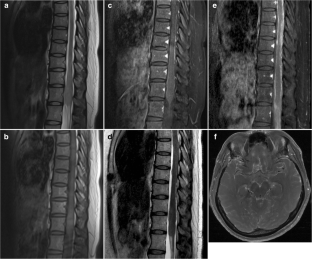

Diffuse midline glioma with histone H3 K27M mutation is a new entity described in the 2016 update of the World Health Organization Classification of Tumors of the Central Nervous System. The purpose of this study was to evaluate the clinical and imaging characteristics to predict the presence of H3 K27M mutation in spinal cord glioma using a machine learning–based classification model.

A total of 41 spinal cord glioma patients consisting of 24 H3 K27M mutants and 17 wild types were enrolled in this retrospective study. A total of 17 clinical and radiological features were evaluated. The random forest (RF) model was trained with the clinical and radiological features to predict the presence of H3 K27M mutation. The diagnostic ability of the RF model was evaluated using receiver operating characteristic (ROC) analysis. Area under the ROC curves (AUC) was calculated.

MR imaging features of spinal cord diffuse midline gliomas were heterogeneous. Hemorrhage was the only variable that was able to differentiate H3 K27M mutated tumors from wild-type tumors in univariate analysis (p = 0.033). RF classifier yielded 0.632 classification AUC (95% CI, 0.456–0.808), 63.4% accuracy, 45.8% sensitivity, and 88.2% specificity.

Our findings indicate that clinical and radiological features are associated with H3 K27M mutation status in spinal cord glioma.